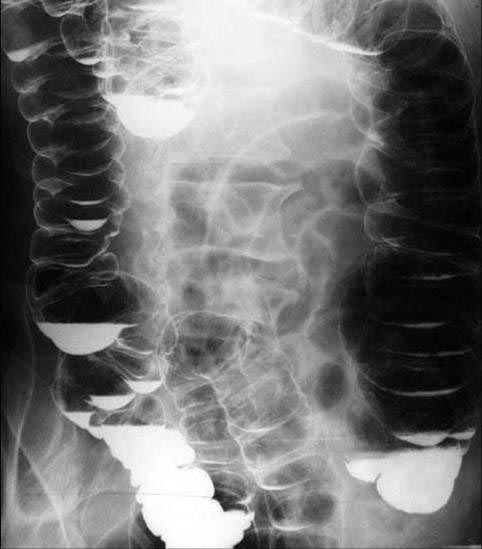

结肠的肿瘤及炎症等引起肠腔狭窄,病变组织因全身或局部原因不能切除,为解决结肠梗阻问题,只能行回肠与结肠的捷径吻合,以解决不同程度肠梗阻。在吻合时,在回横结肠袢式吻合或回乙状结肠双端侧吻合时,回肠不扭转与交叉,直接与结肠吻合,造成逆蠕动吻合。即近端回肠内容物一部分先进入旷置的结肠内,然后再进入远端结肠。如不全梗阻,一部分通过狭窄部分进入旷置的近端结肠,引起一系列病理改变。

盲袢综合征的患者,因近端回肠内容物一部分进入旷置的远端结肠,使这段结肠产生蠕动,将大部分内容物送入远端结肠;还有一部分通过狭窄部位进入临置的近端结肠,这部分内容物,有两个途径排出,一是顺蠕动通过狭窄再次排入远端结肠;二是通过逆蠕动从旷置的远端回肠进入远端结肠。

以上回肠内容物的运行过程使旷置的肠管受到反复刺激及内容物的积存,导致旷置结肠扩张,尤其是狭窄近端。时间稍长则结肠壁增厚,形成肿块,在蠕动通过狭窄部位时,或蠕动时产生腹痛,严重时引起恶心、呕吐等一系列症状。捷径吻合的用意在于使病变病位休息,或对肿瘤刺激减少而生长缓慢,或炎症等病变促其早期消除炎症。如吻合呈逆蠕动方向,则肿瘤生长加速,炎症愈合缓慢。